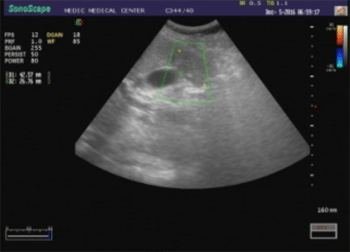

-Chụp đa lát cắt (MSCT_Multislice computed tomography) tổng quát bụng cho thấy gan không to, chủ mô gan đồng nhất. Hạ phân thùy VI gan (P) có thương tổn giảm đậm độ, kích thước 4 x 6cm, đẩy lồi bao gan ra ngoài. Thương tổn dày thành đại tràng ngang gần góc gan, dày khoảng 20mm, bắt thuốc cản quang mạnh và xóa mờ mô mỡ xung quanh. Có vài hạch nhỏ kế cận kích thước 5- 10mm (Hình 2) à Chẩn đoán sơ bộ: Theo dõi ung thư đại tràng ngang xâm lấn xung quanh, di căn hạch và di căn gan. Chẩn đoán phân biệt: Tổn thương gan và đại tràng do ký sinh trùng.

Hình 2. Tổn thương giảm đậm độ gan (P) và dày thành đại tràng ngang